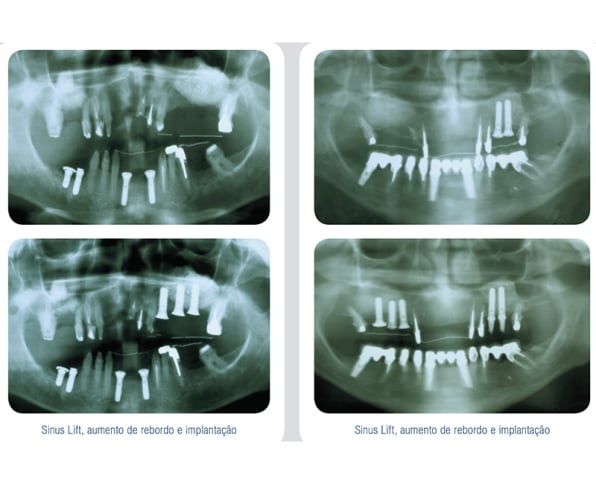

Os produtos OSTEOSYNT vêm sendo cada vez mais utilizados na Implantodontia, nos procedimentos de reconstrução do rebordo alveolar total ou parcialmente perdido, como conseqüência de doenças periodontais, cistos, tumores, traumatismos e consequente perda de elementos e necessidade de sua substituição.

Veja abaixo alguns casos já tratados com as biossoluções EincoBio com resultados de sucesso:

- Preenchimento do seio maxilar (Sinus Lift);